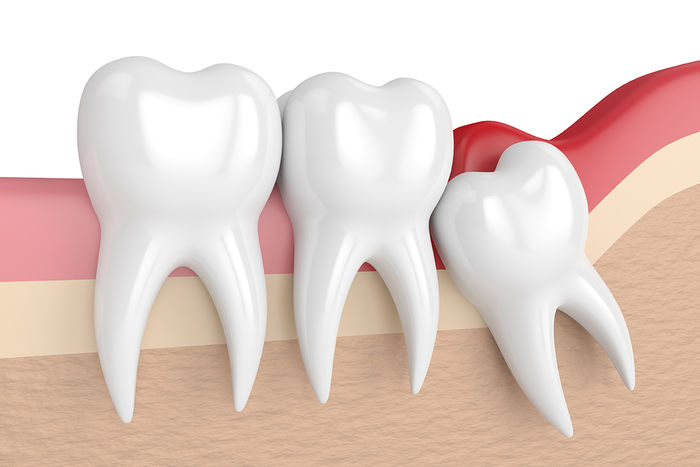

이처럼 노란 색에 동그란 이가 부모 모릅니다. 위의 부모 모르를 카미다 케동이란 공기 주머니와 뿌리가 근처에 있네요위의 부모 모르를 발치할 때 처음 고려하는 것은 얼마나 깊은 매복되어 있습니까. 그리고 환자의 입이 얼마나 잘 열지도 중요합니다. 입의 열림 상태를 “개구량”이라고 합니다.위의 부모 모르면 생각보다 잘 보이지 않습니다. 해도, 입이 열리지 않으면 더 잘 보이지 않고.만약 입이 안 떨어지게 숨은 정도가 심한 경우는 위의 부모 모른다고 해도 난이도가 높아지는 일이 있습니다. 다행히, 이 환자의 위 매복 부모 모르는 경우 난이도가 그렇게 높은 보이지 않습니다. 치아 뿌리도 열지 않기 때문에 몇초에서 날 정도의 난이도요.그 다음, 아래의 부모 모른다.아래의 부모 모르는 경우 가장 중요하게 생각하는 것은 매복 부모 모른다고 신경관까지 거리입니다. 하악 신경과 거리가 가까울수록 발치 난이도는 커졌고 발치 후 합병증도 생길 가능성이 높습니다. 덕양구 부모 모르는 발치과 다라 플랜트로 치과용 CT를 촬영하고 매복 부모 모른다고 신경의 3차원적 위치를 확인합니다.